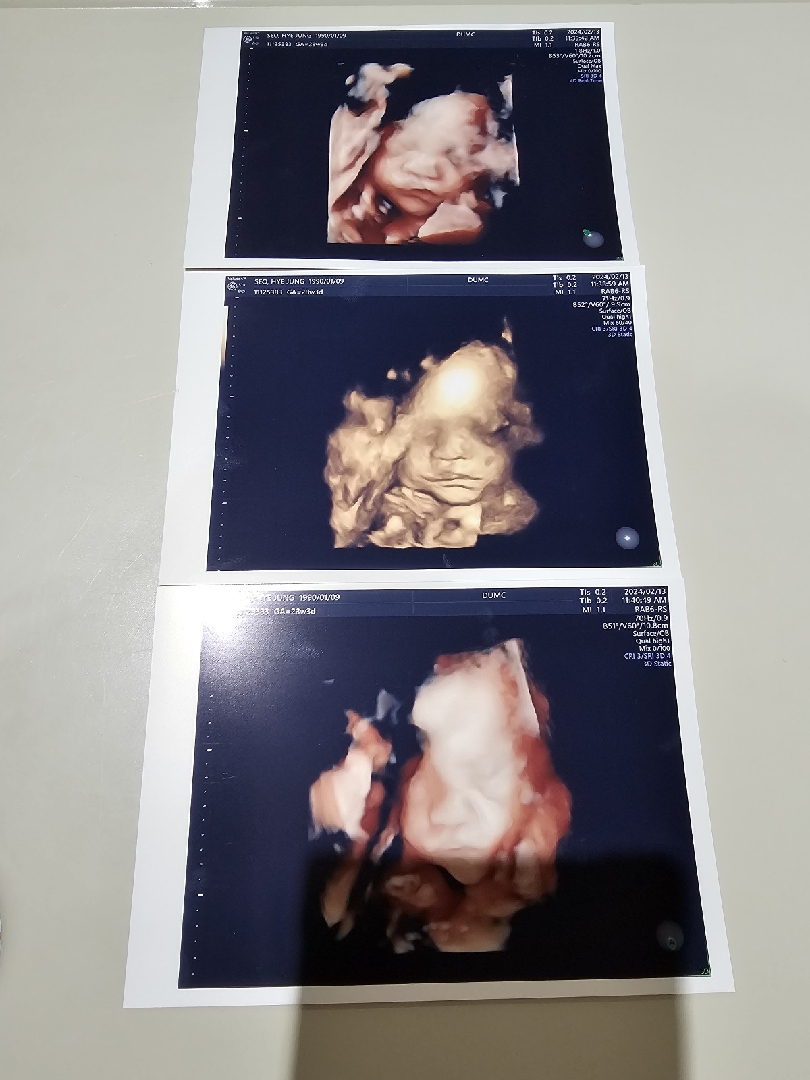

28주차 입촘 성공 했어요ㅎㅎ

처음 보러 갔을땐 손이랑 발로 다 가려버려서 걸어보고 달달한거 먹어 보고 했는데도 안보여서 포기 했다가 드디어 봤어요ㅎㅎ 코만 저고 나머지는 신랑ㅎㅎ